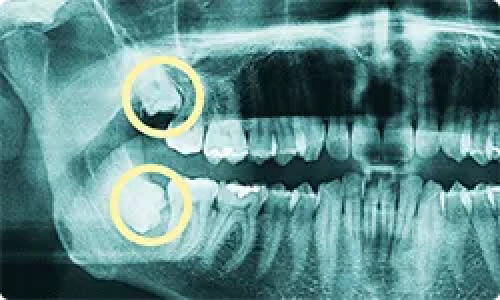

CASE 02

左上下の親知らずを抜きたい

親知らずの生え方

斜め、真横に生えている

抜歯時間

約15分

抜歯費用

約3,000円-5,000円

CASE 03

上下の親知らずを抜きたい

埋まっている

約30分